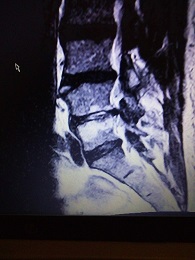

ich hatte vor kurzen ein Kontroll-MRT-LWS, weil bei mir eine Bandscheibenentzündung in DD oder eine Wirbelkörperentzündung. Im Bild im L4/5 ist dort etwas ungewöhnliches zu sehen, was kann das sein?

habe noch paar Bilder gefunden, die in der Sequenz T2W TSE sag; T1W TSE sag; TIR long TE cor

- Bild1.jpg (80.48 KiB) 6503 mal betrachtet

- Bild2.jpg (81.92 KiB) 6503 mal betrachtet

- Bild3.jpg (92.15 KiB) 6503 mal betrachtet

- Bild4.jpg (97.57 KiB) 6503 mal betrachtet

Das mit dem Kontroll-MRT kam auch nur von der HÄ, weil das ein Neurologe empfohlen hat. Weil voriges Jahr in der Stelle L4/5 eine Vermutung geäußert wurde, das im DD eine Diszitis vorliegt und das nach einem Jahr ein Verlaufs-MRT gemacht werden soll.